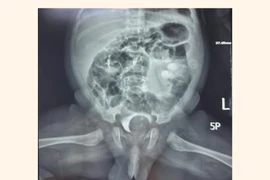

Bàng quang ở người trưởng thành chỉ cần chứa khoảng 500 ml nước tiểu là đã căng to nhưng ở người đàn ông này chứa được hơn 3 lít nước tiểu, gấp 6 lần người thường.

Bàng quang ở người trưởng thành chỉ cần chứa khoảng 500 ml nước tiểu là đã căng to nhưng ở người đàn ông này chứa được hơn 3 lít nước tiểu, gấp 6 lần người thường. Bệnh lý túi thừa bàng quang dễ nhầm lẫn với bệnh lý khác.